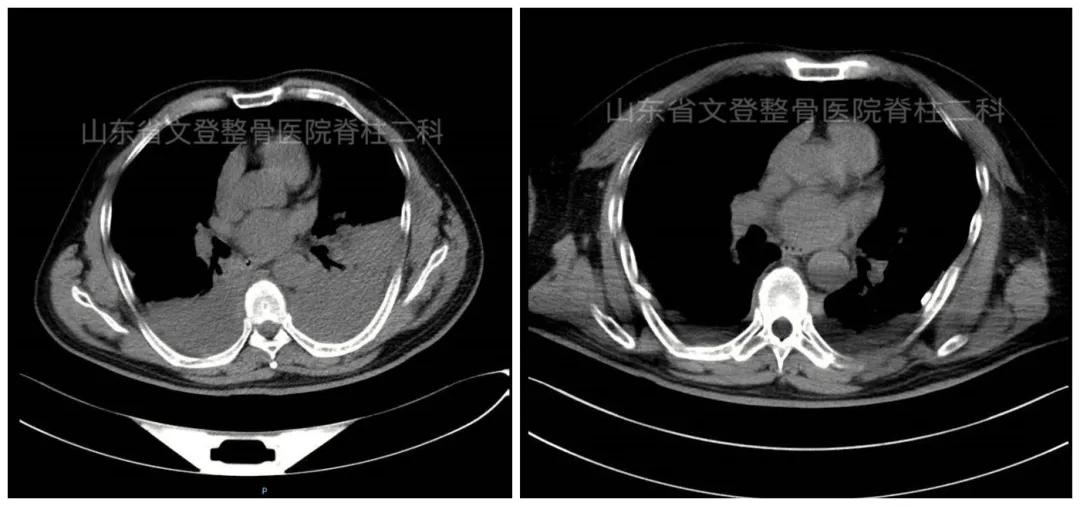

姜传杰主任查看病人认为病情复杂,目前患者面临两个主要问题:一是胸部损伤,二是下肢静脉血栓栓塞。两个原因均可能导致严重并发症,甚至病人死亡,应及时处理。针对患者胸部损伤且多发性肋骨骨折,外科彭志清主任进行了会诊并转入外科行胸腔闭式引流。邹娟主治医师结合CT及时抽取胸腔积液及积气,快速有效的控制了病情。

胸腔积液处理前、后